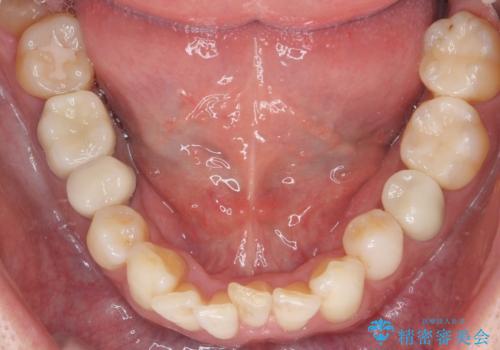

銀歯のやり替えと並行してホワイトニングも行いました。

結果的には銀歯がすべて白くなり、前歯のガタつきもある程度改善され大変喜んでいただけました。

治療終了時からナイトガードを使用していただき、歯ぎしりによる破折を予防しています。